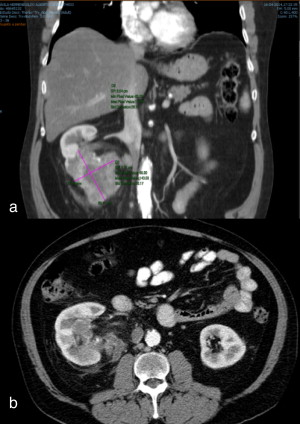

Por motivos económicos, o doente abandona o tratamento e o hospital em agosto de 2013. Passa a ser acompanhado em Portugal, no Hospital Prof. Doutor Fernando Fonseca, e finalmente em fevereiro de 2014 (6 meses depois) é observado em consulta de oncologia e reestadiado. A TAC T‐A‐P revelou uma massa renal com 10,5 cm de maior eixo à direita, com adenopatias lomboaórticas hilares e interaortocava, ainda que sem evidência de metastização pulmonar, hepática ou óssea (fig. 2 ).

TAC toraco‐abdomino‐pélvica de reestadiamento, realizada em Portugal, 6 meses ...

Figura 2.

TAC toraco‐abdomino‐pélvica de reestadiamento, realizada em Portugal, 6 meses após a realização de um ciclo de, sunitinib nos EUA.